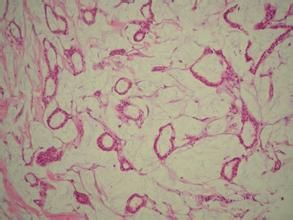

粘液癌(mucoid carcinoma):又稱為膠樣癌(colloid carcinoma),常見於胃和大腸。鏡下,初時粘液聚積在癌細胞內將核擠向一側,使該細胞呈印戒狀,故一般稱之為印戒細胞(signet-ring cell)。當印戒細胞為主要成分呈廣泛浸潤時則稱印戒細胞癌。